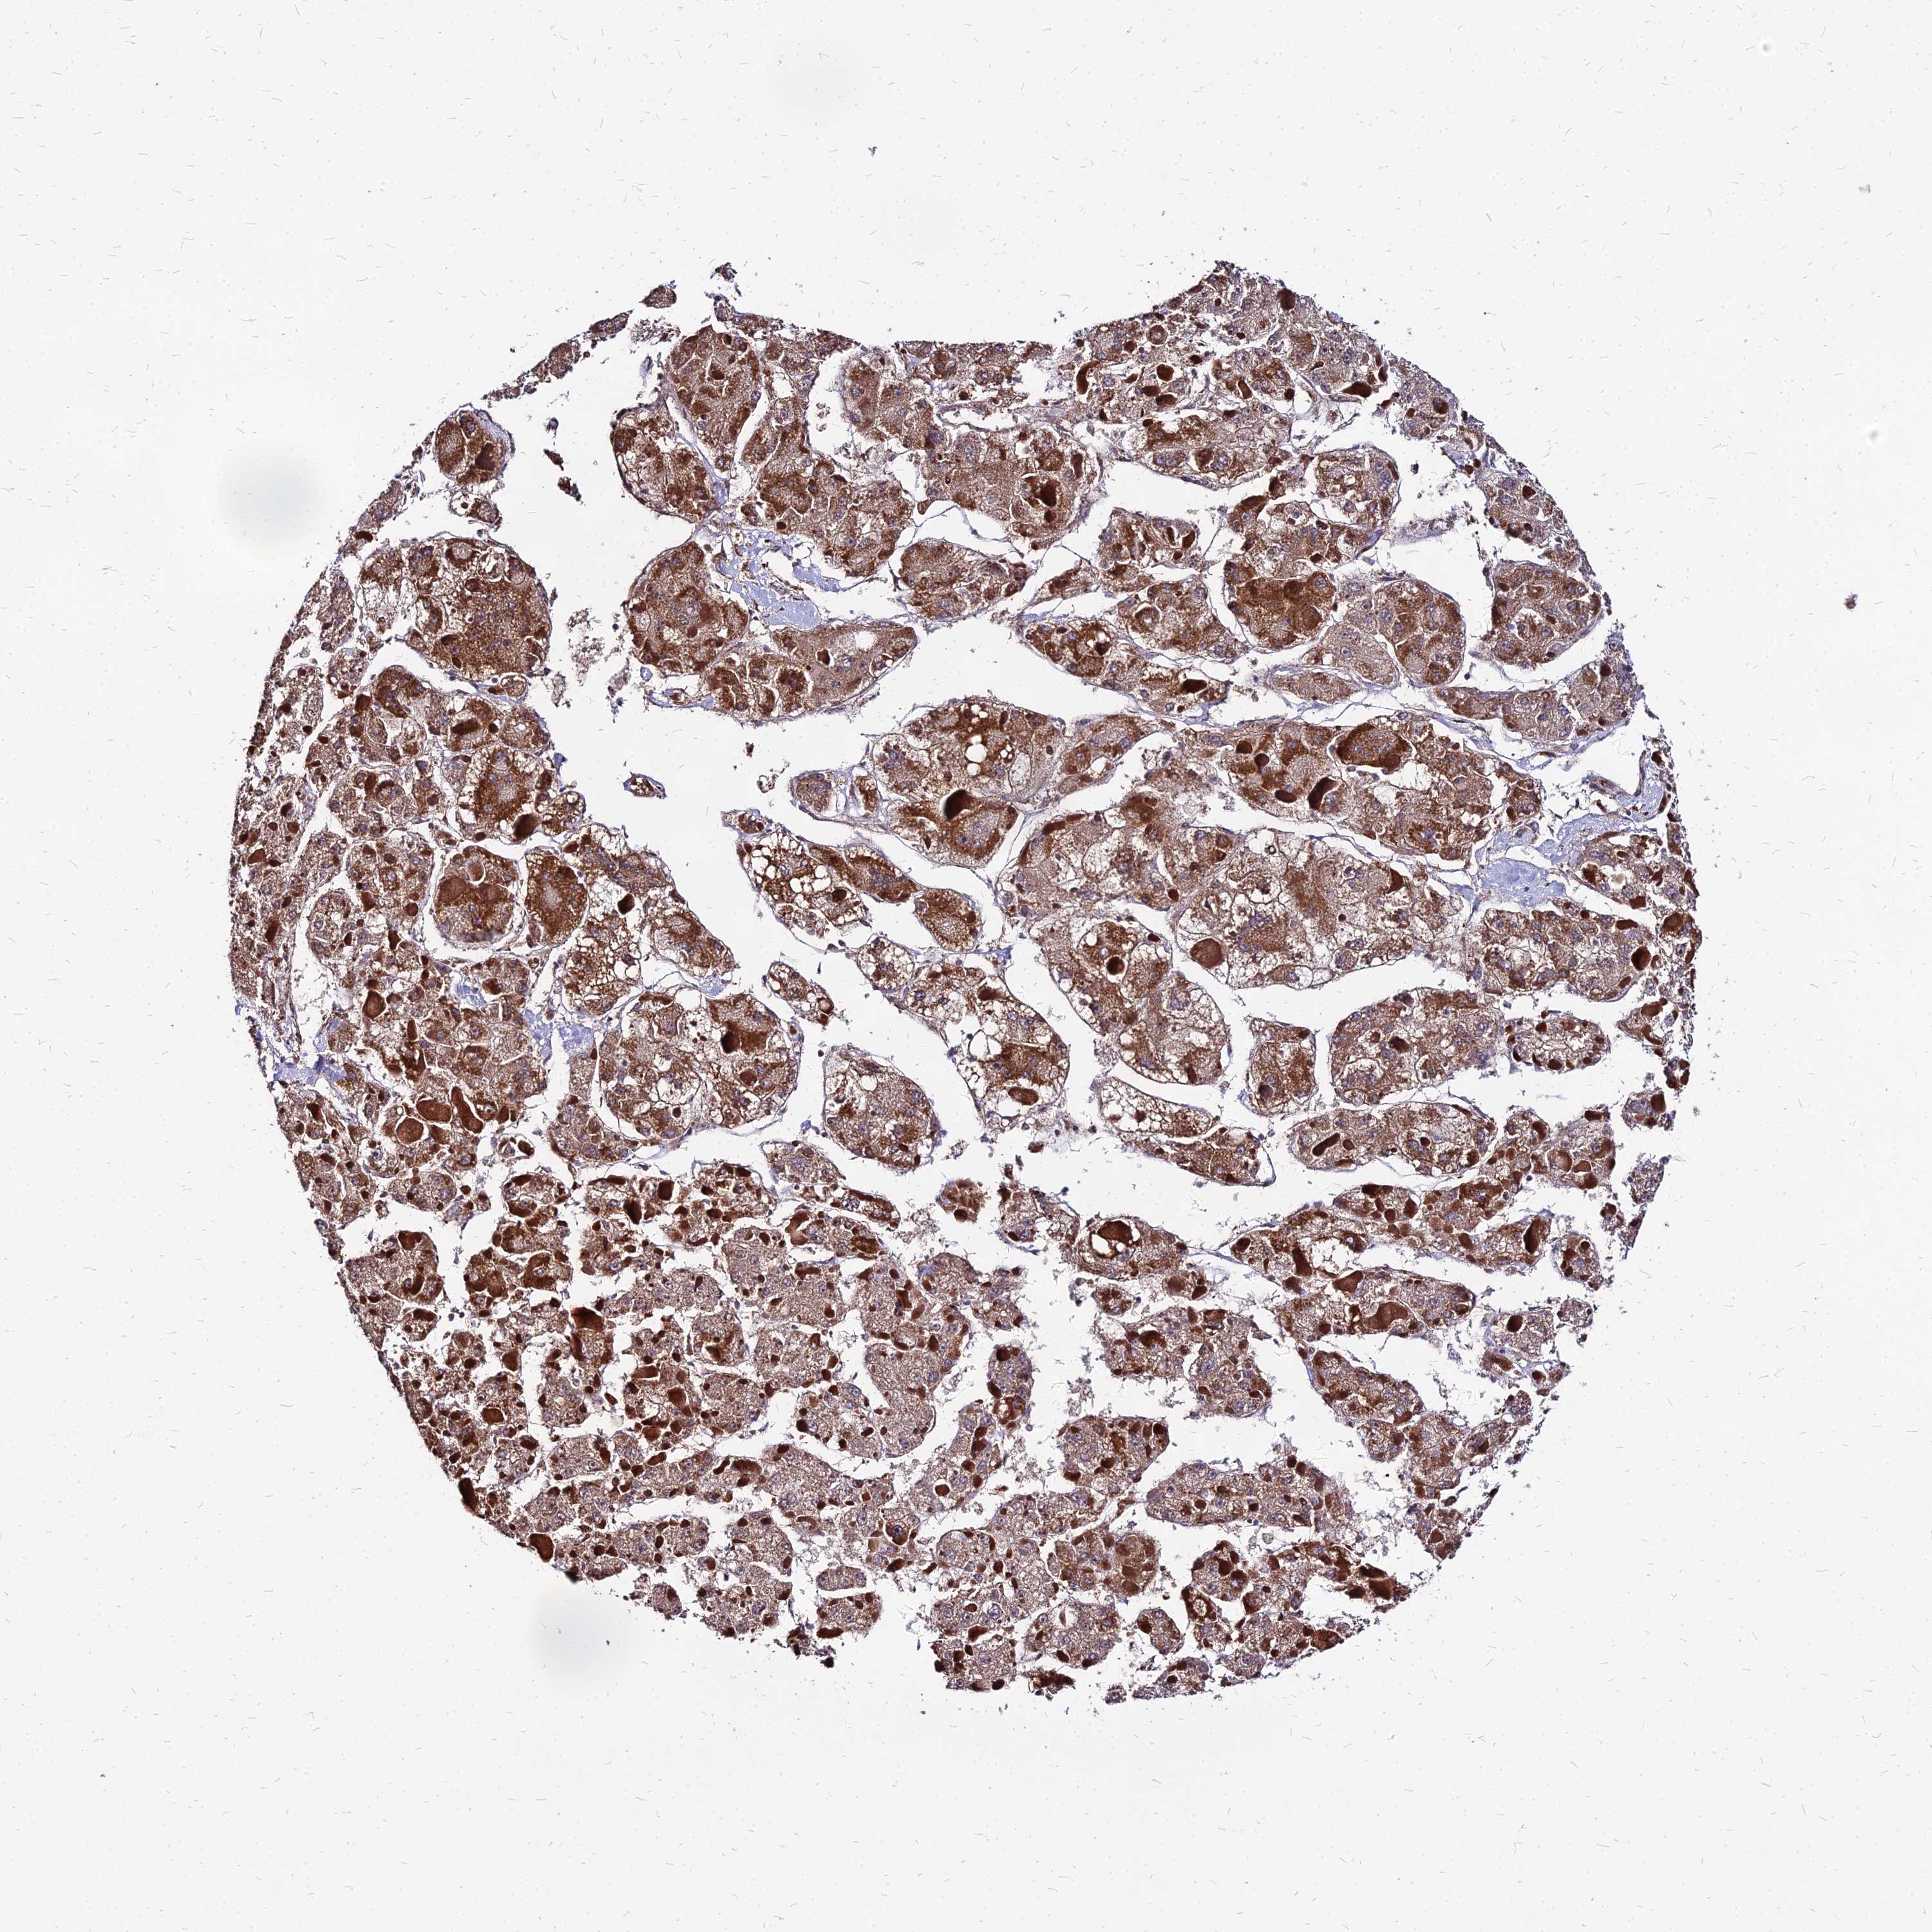

DLD